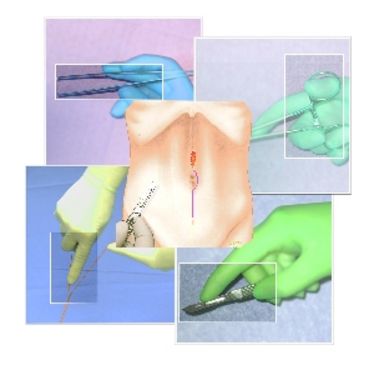

Hands-on-Kurs - Multiorganentnahme

Hands-on-Kurs - Multiorganentnahme

OP-Kurs "Mikrochirurgie der peripheren Nerven und Gefäße"

OP-Kurs "Mikrochirurgie der peripheren Nerven und Gefäße"